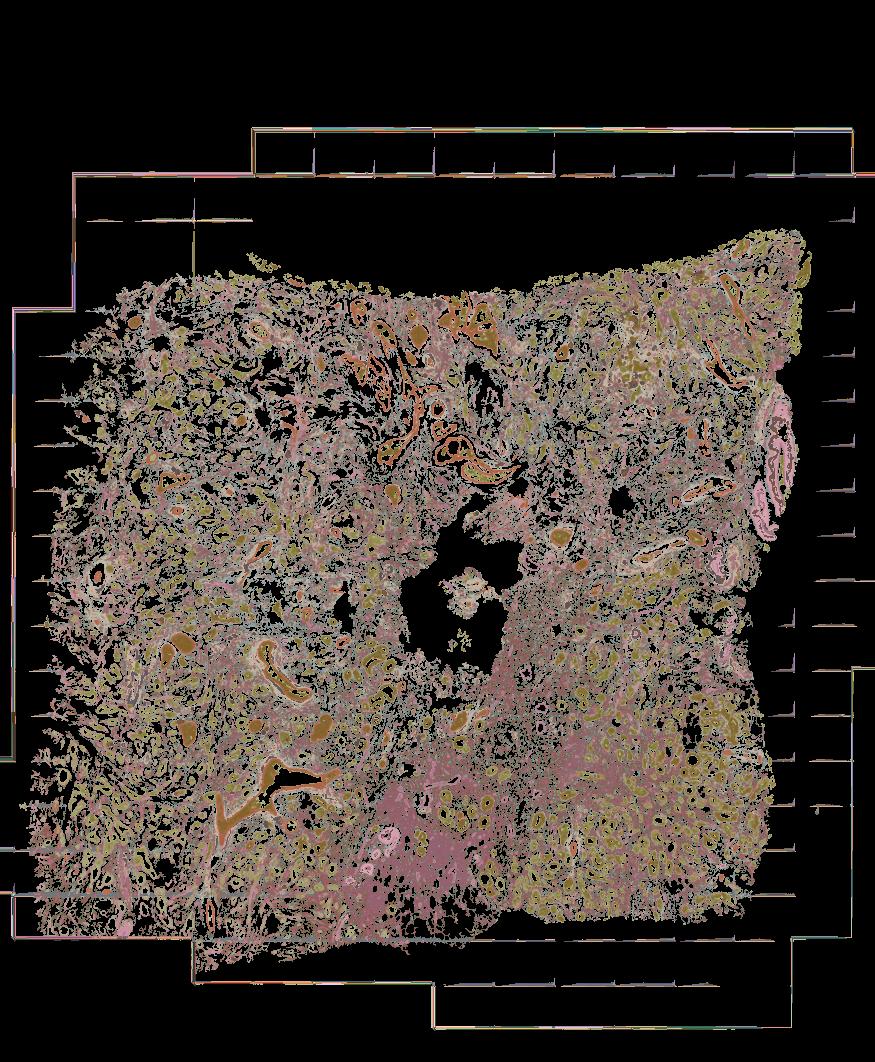

Atlas: Washington University

Breast cancer (BC) is defined by distinct molecular subtypes with different cells of origin. The transcriptional networks that characterize the subtype-specific tumor-normal lineages are not established. In this work, we applied bulk, single-cell and single-nucleus multi-omic techniques as well as spatial transcriptomics and multiplex imaging on 61 samples from 37 patients with BC to show characteristic links in gene expression and chromatin accessibility between BC subtypes and their putative cells of origin. Regulatory network analysis of transcription factors underscored the importance of BHLHE40 in luminal BC and luminal mature cells and KLF5 in basal-like tumors and luminal progenitor cells. Furthermore, we identify key genes defining the basal-like (SOX6 and KCNQ3) and luminal A/B (FAM155A and LRP1B) lineages. Exhausted CTLA4-expressing CD8+ T cells were enriched in basal-like BC, suggesting an altered means of immune dysfunction. These findings demonstrate analysis of paired transcription and chromatin accessibility at the single-cell level is a powerful tool for investigating cancer lineage and highlight transcriptional networks that define basal and luminal BC lineages.